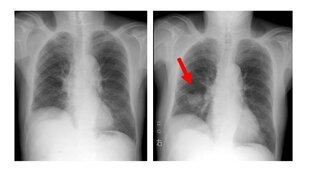

Yahoo!知恵袋右肺上野小結節ってなんですか?今日、会社の健康診断の結果をもらったのですが、

胸部X線検査の欄に「異常なし。但し、右肺上野小結節。(不変)。」と記載してありました。